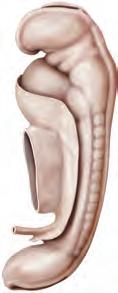

Stadi 10-12 (settimana 4) In tutti gli stadi continua lo sviluppo dei somiti: durante lo stadio 10 si contano 4-12, allo stadio 11 (AB) 13-20 (AB1) e allo stadio 12 21-29 somiti. Nello stadio 10 le creste neurali (AB2) iniziano a fondersi per dare il tubo neurale. Dall’estremità anteriore del tubo neurale origina l’encefalo, da quella posteriore il midollo spinale. Cranialmente e caudalmente il tubo neurale rimane ancora aperto, con il neuroporo anteriore (AB3) e il neuroporo posteriore (AB4). Nello stadio 11 l’embrione è curvato e provvisto di una piega cefalica (B5) e di una piega caudale (B6), e risultano visibili sia le prime due coppie di archi branchiali (B7) sia la vescicola ottica. Il neuroporo anteriore si chiude. Nello stadio 12 si contano tre coppie di archi branchiali, il neuroporo posteriore si chiude e si riconosce la fossetta acustica. L’abbozzo cardiaco è formato da un’ansa, che inizia a manifestare attività contrattili. Si sviluppano gli abbozzi degli arti superiori.

Stadi 13-15 (settimana 5) L’embrione è fortemente curvato e possiede 30 o più somiti (il numero preciso è difficilmente determinabile). Nello stadio 13 sono visibili quattro coppie di archi branchiali, il placode del cristallino è abbozzato e si sviluppano gli abbozzi degli arti inferiori. Nello stadio 14 è possibile riconoscere sia il cristallino sia la fossetta nasale; si è formato il calice ottico e il differenziamento degli arti prosegue. Nello stadio 15 si sono sviluppate le vescicole encefaliche e l’abbozzo della mano.

Stadi 16-18 (settimana 6) Tali stadi sono caratterizzati da ulteriori differenziamenti degli arti: si forma l’abbozzo del piede (C8 ) e delle dita della mano (C9). Nello stadio 18 il gomito è riconoscibile e si sviluppano le dita dei piedi. Ha inizio l’ossificazione negli abbozzi ossei mesenchimali. Allo sviluppo della faccia contribuiscono la formazione dei tubercoli auricolari, quella del solco nasolacrimale, la formazione della punta del naso e delle palpebre e la pigmentazione degli occhi.

Stadi 19-20 (settimana 7) L’embrione risulta meno curvato, poiché il tronco si è allungato ed esteso e, rispetto al tronco, la testa si è ingrandita. Anche gli arti si allungano e si accrescono oltre l’abbozzo cardiaco, disponendosi ventralmente. A causa di mancanza di spazio nella cavità addominale dell’embrione, le anse dell’intestino medio vengono dislocate nel cordone ombelicale.

Stadi 21-23 (settimana 8) Gli stadi dell’ultima settimana del periodo embrionale sono caratterizzati dal differenziamento dei tipici caratteri umani. La testa risulta meno curvata e si sviluppa il collo (D10). Si sviluppano inoltre l’orecchio esterno (D11) e le palpebre (D12). Gli arti si allungano, le dita (D13) sono formate da più falangi e risultano reciprocamente separate. Si sviluppano le dita dei piedi e ha inizio l’ossificazione condrale. In corrispondenza dei genitali esterni si manifestano specifiche differenze di sesso.

9a-12a settimana A causa del rapido accrescimento dimensionale, entro la fine della 12a settimana la LVC raddoppia. In rapporto al tronco, il collo e gli arti, in particolare quelli superiori, aumentano (A). La faccia assume tratti maggiormente caratteristici, poiché gli occhi, inizialmente collocati su un piano piuttosto laterale, migrano in direzione ventrale e gli orecchi assumono la loro posizione definitiva ai lati della testa. Le palpebre aderiscono le une alle altre, chiudendo la rima palpebrale. Entro l’11a-12a settimana, le anse intestinali collocate nel cordone ombelicale si riportano nella cavità addominale ora più spaziosa. Nella 12a settimana ha luogo il definitivo differenziamento tra organi genitali esterni maschili e femminili.

13a-16a settimana Tale periodo è caratterizzato da un accrescimento estremamente rapido del tronco, del collo e degli arti. La testa si solleva. Il corpo si copre di sottili peli, la lanugine, e il tipo di capigliatura diventa riconoscibile. L’ossificazione procede, cosicché nel feto di 16 settimane (B) le ossa sono riconoscibili in radiografia.

17 a-20 a settimana L’accrescimento del feto rallenta nuovamente e durante tale periodo l’aumento di peso è scarso. Anche i segmenti degli arti inferiori hanno raggiunto le loro proporzioni definitive (C). Le ghiandole sebacee secernono una sostanza grassa e biancastra, la vernice caseosa, che protegge la cute del feto dalla macerazione causata dal liquido amniotico. Si sviluppano i capelli e le sopracciglia. In tale periodo la madre percepisce per la prima volta i movimento del feto ed è consigliabile effettuare un esame ecografico di routine (D).

21a-25a settimana L’aumento di peso continua. Tuttavia, poiché i cuscinetti adiposi sottocutanei non si sono ancora formati e la cute si ac-

cresce rapidamente, il feto presenta un aspetto rosso e grinzoso. Si sono sviluppate le unghie, la faccia e il corpo hanno assunto l’aspetto di un feto al termine di gravidanza. Tuttavia, di regola soltanto i feti partoriti dopo la 25a settimana riescono a sopravvivere, poiché solo a partire da questo momento il sistema respiratorio è sufficientemente sviluppato per iniziare la sua attività funzionale.

26a-29a settimana In seguito allo sviluppo dei cuscinetti adiposi sottocutanei, il corpo diventa più rotondo e robusto e aumenta notevolmente di peso. Le palpebre si separano, cosicché gli occhi sono nuovamente aperti (D). Le sopracciglia e le ciglia sono ben sviluppate. I capelli si allungano. In linea di principio, a partire da questo periodo i feti partoriti prematuri sono capaci di sopravvivere.

30 a-34 a settimana L a percentuale di tessuto adiposo sottocutaneo aumenta ulteriormente rispetto al peso corporeo; anche gli arti superiori e inferiori si irrobustiscono e la pelle assume un colore roseo. Le unghie della mano si sono accresciute fino alla punta delle dita, mentre quelle dei piedi iniziano appena a formarsi. Nei feti di sesso maschile i testicoli iniziano a discendere (discesa dei testicoli).

35a-38a settimana Nell’ultimo mese di gravidanza, soprattutto il tronco del feto aumenta di larghezza. In corrispondenza della parete addominale, il punto di inserzione del cordone ombelicale è migrato al centro. Le unghie delle dita dei piedi raggiungono l’estremità delle dita e i peli della lanugine cadono, cosicché la cute è rivestita solamente dalla vernice caseosa. Nel feto di sesso maschile, i testicoli migrano nello scroto, mentre nel feto di sesso femminile le ovaie sono ancora collocate al di sopra della piccola pelvi.